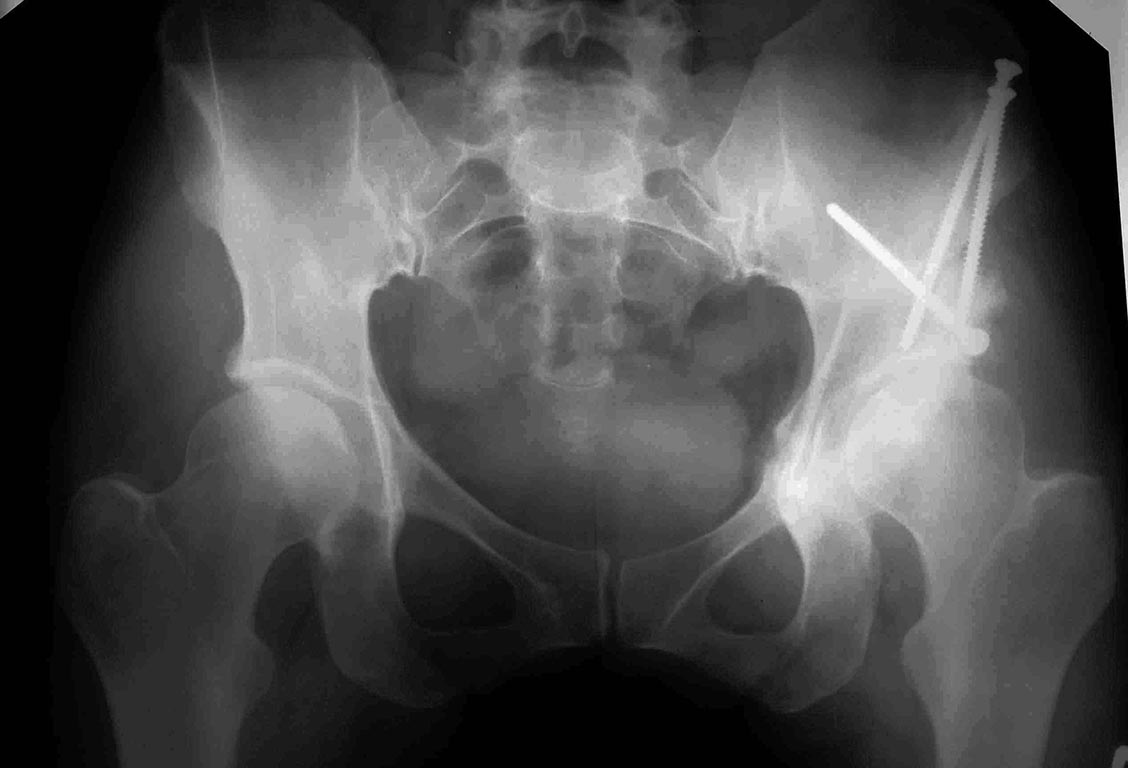

Пациентка 40 лет оперирована по-поводу дисплазии т/б сустава - ПАО,

огромное спаибо нашим

коллега из Н.Н., честно, без иронии. Сейчас 6 мес после операции,

появилась боль, по тестам,

похоже на импинджемент. Имеет ли смысл за ним гоняться? Или

рекомендовать поверхностное или тотальное протезирование?